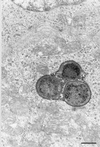

In vitro or animal models have been used to investigate the pathogenesis of Helicobacter pylori infection. However, extrapolation to humans of results obtained with these heterologous models remains difficult. We have developed a new model for the study of H. pylori infection that uses human entire embryonic stomachs engrafted in nude mice. At 80 days after implantation, 22 of these xenografts, which exhibited a mature gastric epithelium, were inoculated with 10(7) to 10(8) CFU of either H. pylori LB1, a freshly isolated H. pylori strain (n = 12), or H. pylori ATCC 49503 (n = 10). After 12-week examination, H. pylori LB1 persistently colonized the antrum of all inoculated grafts, as assessed by culture (mucus and mucosa), immunohistochemistry (mucosa), and a rapid urease test (mucus). H. pylori ATCC 49503, either before or after in vivo passage, permitted only a transient 2-week colonization in one of the five inoculated grafts in both groups. Colonization was always associated with an increase of gastric juice pH. A mild neutrophil infiltration of the gastric mucosa was noted solely in infected grafts. Transmission electron microscopy showed adherence of H. pylori organisms to epithelial cell surface. In six animals, intracytoplasmic location of this bacterium was observed in the antrum or the fundus. These results allow us to propose this model as a new ex vivo model for the study of specific H. pylori-gastric cell interactions.